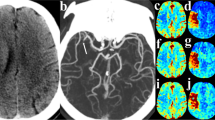

CT number results from phantom scans are summarized in Fig. 2. A clear increase in CT number by 3–5 HU was found with the standard mCTA scan protocol compared to that of the standard NCCT protocol. mCTA CT number overestimation was greater near the skull as opposed to more medial regions; that is, CT number inconsistency was spatially dependent. Increased CT number was also found when scanning with the standard NCCT protocol at 40 mm beam collimation width compared to 20 mm while keeping all other scan parameters unchanged. Furthermore, using a modified mCTA-P protocol, which changed the mCTA beam collimation width to 20 mm, better CT number consistency was achieved between NCCT and mCTA. Based on these findings, prior to calculating perfusion maps, a zeroth-order bias correction was applied by subtracting 4 HU in the brain voxels of real mCTA images in our dataset, which were acquired with the standard mCTA scan parameters. The effect of CT number bias correction on calculated mCTA-P maps is illustrated in Supplemental Fig. 3. An example of model fitted TDCs for CTP, dCTP, and mCTA-P are shown in Supplemental Fig. 4.

Region of interest (ROI) segmentations overlaid on a CT scan of an anthropomorphic head phantom (top left). In each plot, the line colour corresponds to the colour of the ROI in the segmentation. A substantial 3–5 HU increase in CT number is seen between the standard non-contrast CT (NCCT, 20 mm beam collimation width) and standard multiphase CT angiography (mCTA, 40 mm) protocols at all ROIs (top right). The effect of beam collimation width was isolated by scanning with the NCCT protocol at 20 mm and 40 mm beam collimation, which showed a similar increase in CT number at 40 mm (bottom left). A modified mCTA-perfusion protocol was tested in which mCTA beam collimation width was decreased to 20 mm to match that of NCCT, which substantially improved CT number consistency between NCCT and mCTA images (bottom right).